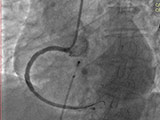

患者男性,84岁,近1个月反复心前区疼痛,伴呼吸困难,经河北燕达医院医疗院长卢长林主任确诊为:严重冠心病,不稳定心绞痛,入院后随即开通急诊绿色通道,为患者快速实施冠状动脉造影检查,冠脉造影示:严重冠脉三支血管病变伴严重钙化

心内科有句俗话:“天不怕地不怕,就怕冠脉有钙化!”怎么回事呢?就是冠心病患者的动脉血管壁,钙化严重,壁垒重重,难以获得理想的支架扩张效果。想要治疗这种病变的血管,需要一种高难度的技术——冠状动脉旋磨术。冠状动脉旋磨术就是用一枚直径1.5毫米、嵌有钻石颗粒的橄榄